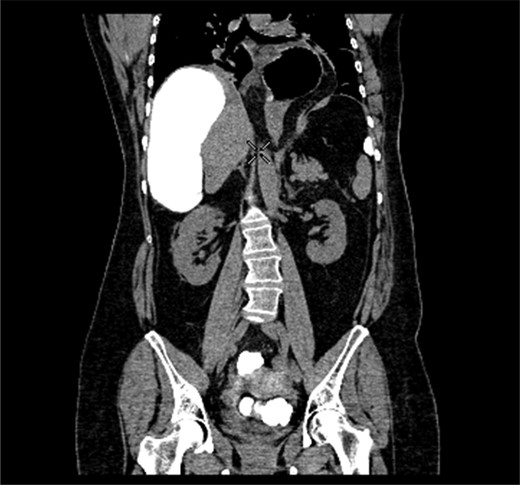

A 58-year-old female with a past medical history of a large intrathoracic hiatus hernia presented to her general practitioner and was subsequently referred to our surgical department with symptoms of sudden onset severe epigastric pain associated with vomiting and abdominal distension. Her abdomen was generally tender, maximally in the epigastric region, although she was not peritonitic. The admission erect chest radiograph showed a large hiatus hernia and an elevated right hemidiaphragm with a large loop of distended bowel (Fig. 1). Subsequent computed tomography (CT) scan demonstrated an almost completely intrathoracic stomach with a degree of volvulus, and the liver medially displaced by a loop of large bowel felt to be caecum (Fig. 2). Since the patient remained otherwise well, bidirectional endoscopy was performed, and given that a volvulus point could not be identified and the ileocaecal junction was not identified, contrast studies were requested (Figs 3–5) which demonstrated an incomplete obstruction caused by a volved caecum rotated anteriorly and cephalad.

Coronal section of contrast-enhanced CT demonstrating contrast filling upwardly displaced caecum.

Axial section of contrast-enhanced CT demonstrating ‘whirl sign’ at the point of volvulus.

After the contrast study partial resolution of symptoms occurred but given the development of free fluid in her contrast CT scan, the decision was taken to manage her surgically. A midline laparotomy was performed, with the finding of a freely mobile, grossly distended caecum flipped anteriorly over the ascending colon as demonstrated on her CT scan (Fig. 6). This was therefore removed with a right hemicolectomy and primary ileo-colic anastomosis. Additionally, there was no evidence of a gastric volvulus (suggesting partial twisting) and since her stomach was completely intra-abdominal, there was no need to address her hiatus hernia at that point in time. The patient was admitted to the high dependency unit post-operatively, made a good recovery and was discharged home within a week of surgery.

Radiological imaging is useful in diagnosing caecal volvulus. Rosenblat et al. [8] found that CT findings of whirl, ileocaecal twist, transition points, X marks the spot and split wall have high specificity for caecal volvulus. Additionally, they found that the absence of distal colonic decompression made the diagnosis of caecal volvulus unlikely. Diagnostic confusion may exist between sigmoid and caecal volvulus; however, the location of the mesenteric twist (CT whirl sign) is highly accurate in distinguishing the two [9]. This whirl sign, as first published by Fisher [10], describes ‘swirling strands of soft tissue attenuation within a background of fat attenuation and gives the appearance of a hurricane on a map’. Barium enema has been historically used to confirm the presence of a volvulus, assess the distal colon and may also have a therapeutic effect [3].